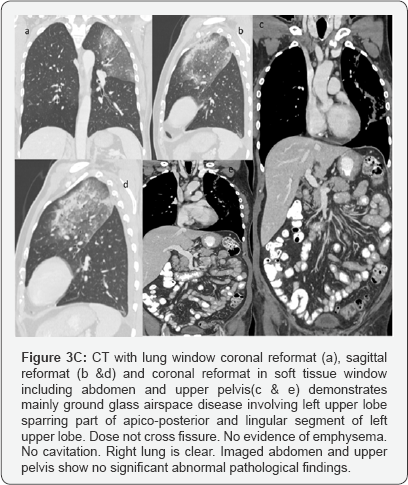

C. CT recommended to exclude underlying pathology /further evaluation considering patient age (Figure 3).

Impression: of Figure 3

CT with Contrast done after 4days of second X-ray chest.

Large area of consolidation seen involving left upper lobe with central area of ground glass opacity surrounded by rim of more density mainly at anterior aspect representing incomplete reversed halo sign.

Multiple prominent enhancing mediastinal lymph nodes. Minimal left pleural effusion. Right lung is clear.

In short term worsening and in view of history, likely community acquired pneumonia.

No mass.